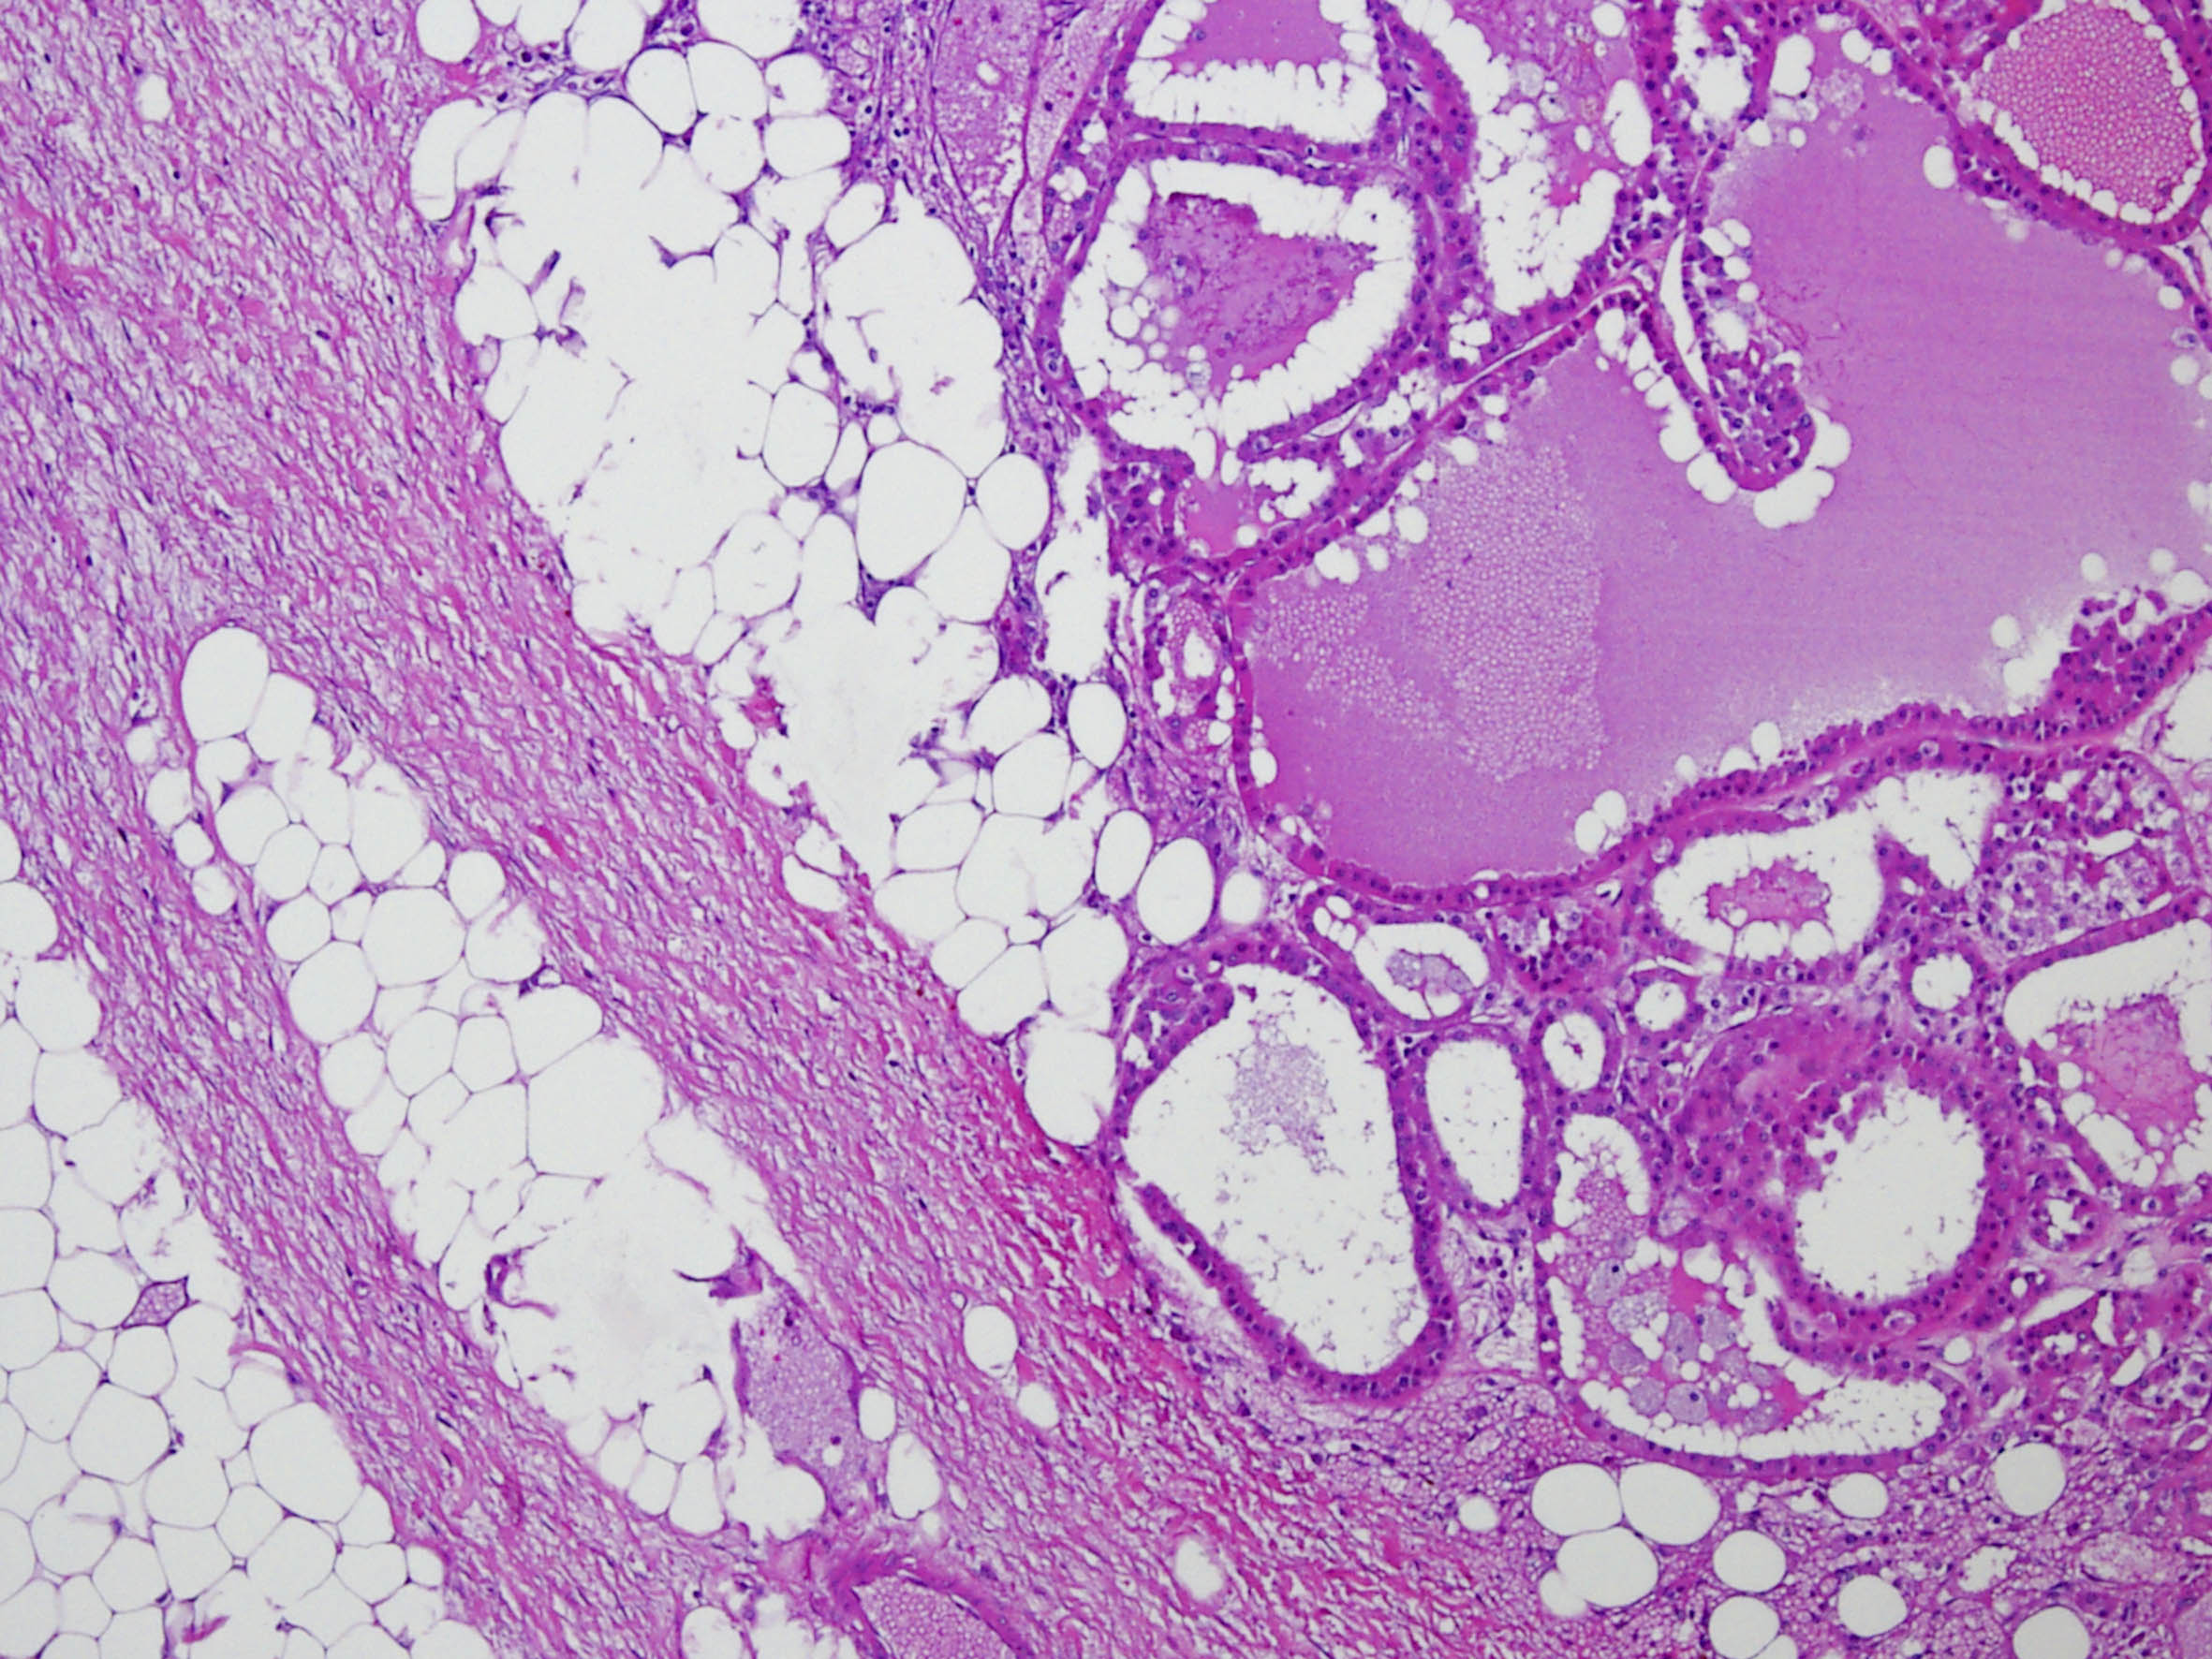

Renal tumor grading

Case ID: 290